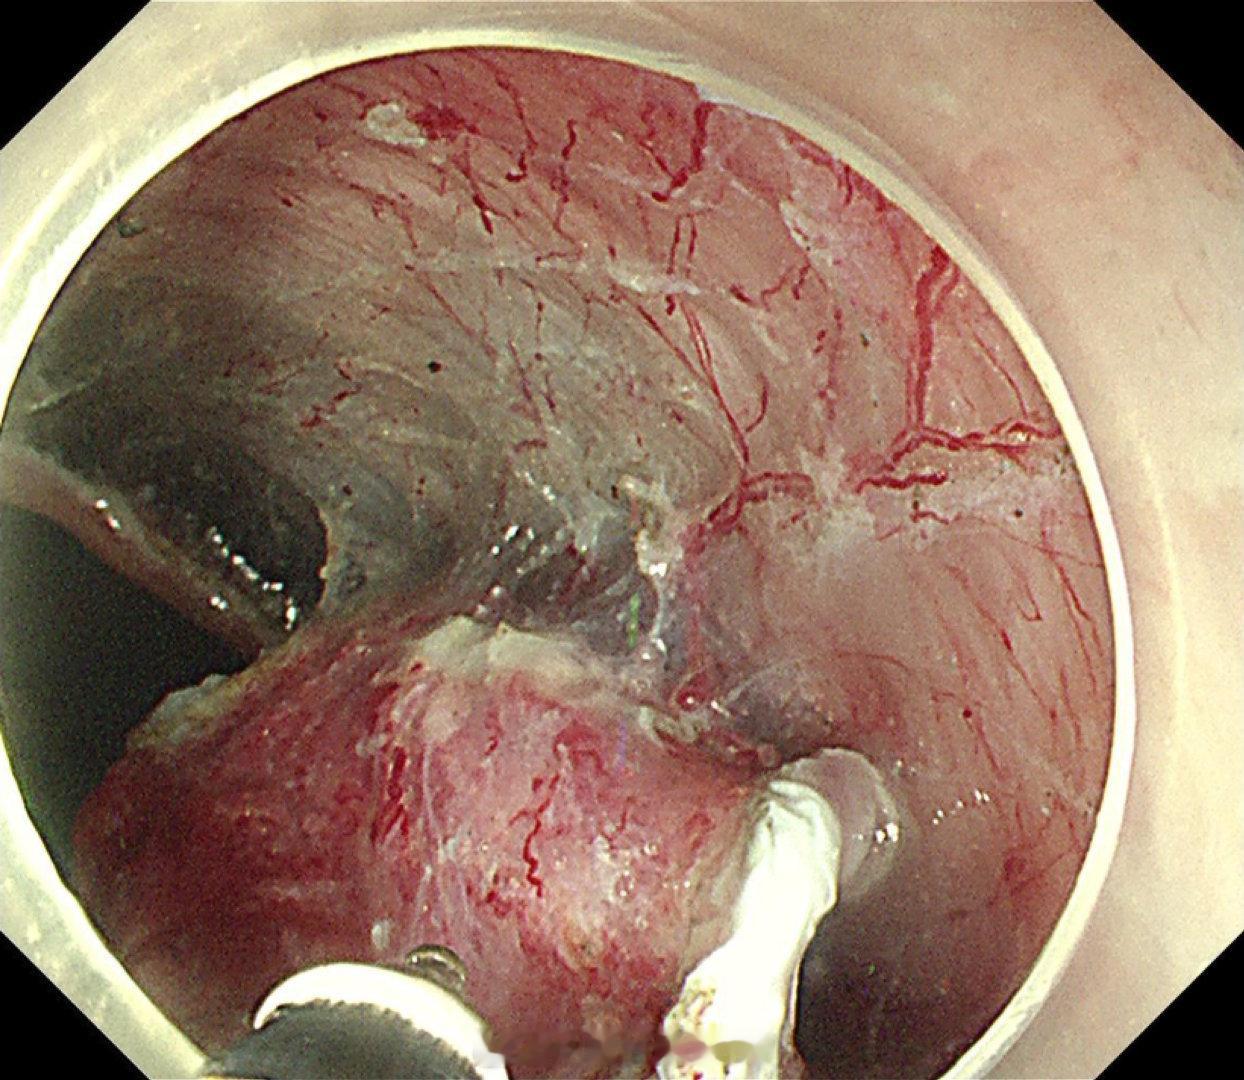

这是个兄弟医院做的内镜发现有贲门病灶,老人体型腹型肥胖很典型,返流持续那么多年导致的Barrett食管癌风险肯定是最高的,她女婿找我精查会诊了一次,我看着病灶虽小,但是有点僵硬,感觉已经到了黏膜下的barrett食管癌,但是他们都想尝试切除看看浸润深度,诊断性esd实施后黏膜下550微米,一般来说这地方超过500微米已经是sm2,淋巴结转移风险急剧加大了,后面就要纠结要不要追加外科手术,但是这个手术做了生活质量会相当不好。所以这种癌的最好措施是预防,发现非常困难,往往一发现就是深了。腹型肥胖的人群减重以减少返流是很重要的。